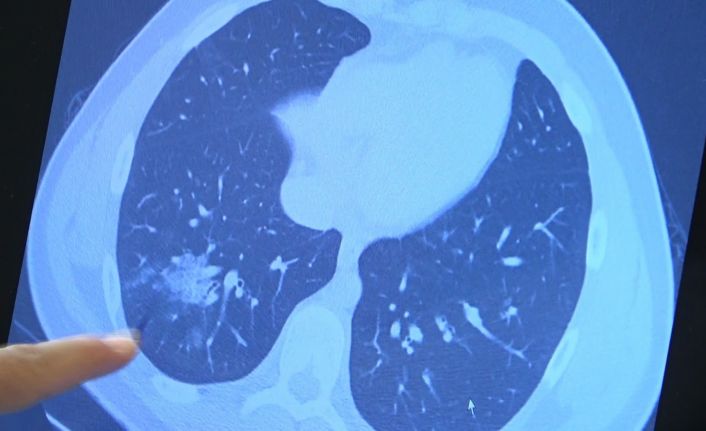

Bazı vatandaşlar hâlâ aşı olmakta tereddüt etmeye devam ederken korona virüs çocuk grubundaki hastaları da etkilemeye başladı. VM Medical Park Samsun Hastanesi Göğüs Hastalıkları Kliniği’nden Prof. Dr. Şevket Özkaya ise aşı olabilecek yaş grubundaki çocukların bir an önce aşılanması gerektiğine vurgu yaptı. 14 yaşında, kronik rahatsızlığı olan ve akciğerlerinde tahribattan dolayı ciddi öksürük, ateş ve nefes darlığı çeken bir hastanın akciğerlerini inceleyen Prof. Dr. Özkaya, "14 yaşındaki kronik rahatsızlığı mevcut olan bir genç hastamızda ciddi akciğer tutulumları var. Her iki akciğerinde de yaygın buzlu cam ve konsolidasyon alanları var. Bu yaştaki çocuklarda beklemediğimiz bir durumdur. Okullarımızda da bu risk var. Okullarımızın açık kalmasının ve sağlık sistemimizin kitlenmemesi için mutlaka aşı olmalıyız. Çocuklarımıza rol model olmalıyız. Şu anda hastanelerimiz hastalara yetişebiliyor. Yatak sayımız yeterli. Ancak kontrollü sosyal hayatımızı düzene sokmadıkça ve aşı olmadıkça, gelecekte hastanelerde yatak sayısı sıkıntısı çekebiliriz" dedi.